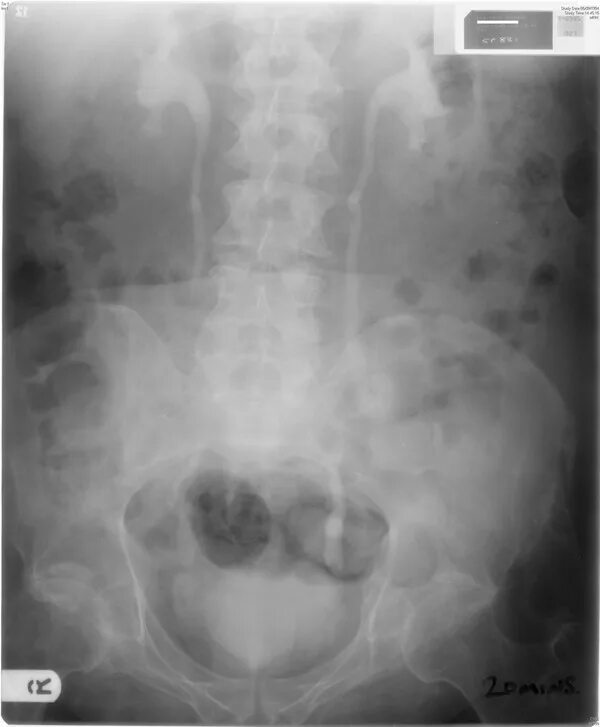

Гидронефроз почки после операции